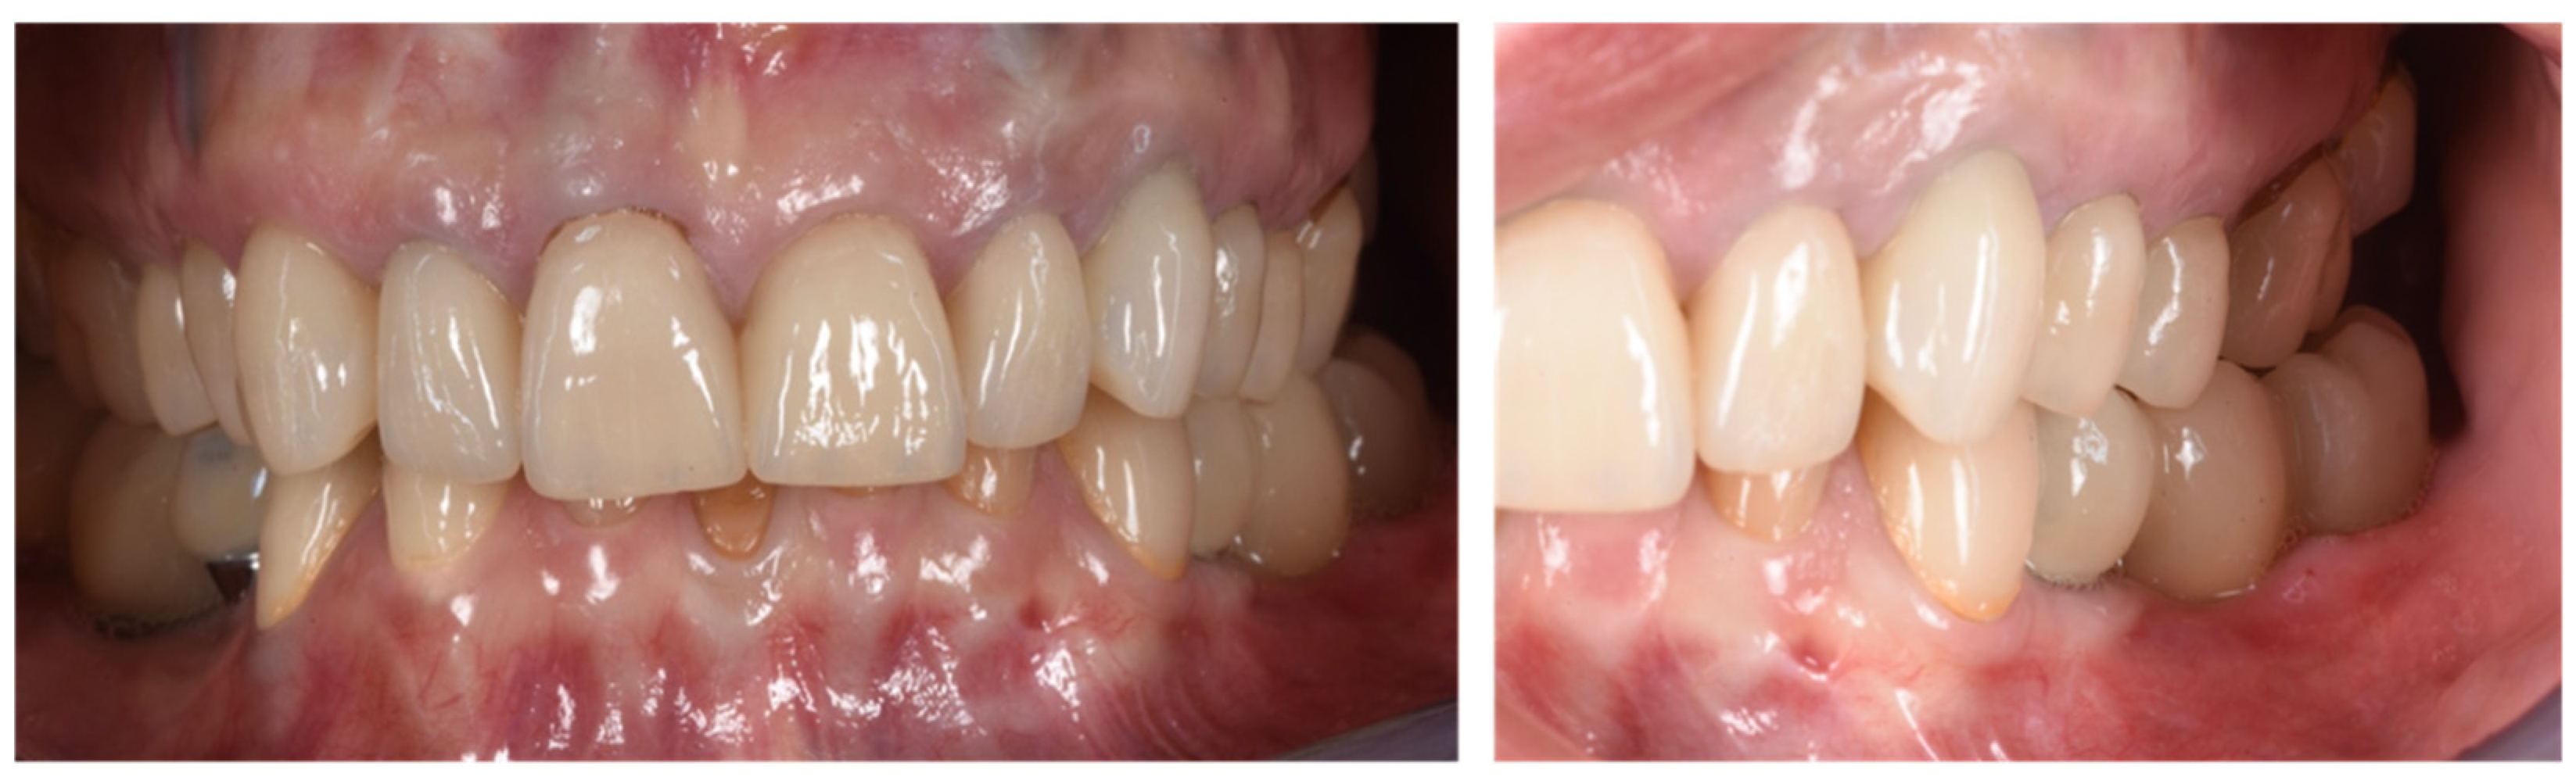

Figure 10.

Clinical evaluation after 18 months of prosthetic loading.

Figure 11.

Scan taken after 18 months of prosthetic loading.

Two implants (Institute Straumann, Basel, Switzerland) of 4 × 12 mm and 5 × 8 mm were inserted in the 3.4 and 3.6 areas, respectively (Figure 9a). The final prosthesis was manufactured with a digital workflow and delivered after three months. The patient was monitored with clinical and radiographic evaluations 12 and 18 months after prosthetic loading. The clinical examination and the digital scans at 12 months of follow-up proved the efficacy of the regenerative approach (Figure 10 and Figure 11). The comparison between 12 (Figure 9b) and 18 month (Figure 9c) radiographs showed stability of the bone crest around the dental implants. Furthermore, a progressive mineralization of the regenerated area was also evident (Figure 9a–c).